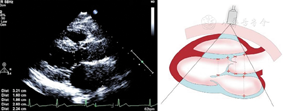

胸骨上窝主动脉弓长轴切面(图24图25)

图24

胸骨上窝主动脉弓长轴切面,显示收缩末期主动脉弓和降主动脉内径测量方法,主动脉弓内径测量位置为无名动脉与左颈总动脉开口位置之间,降主动脉内径测量位置为左锁骨下动脉远心端1 cm处

图25

胸骨上窝主动脉弓长轴切面,显示收缩期主动脉弓峡部峰值血流速度测量方法,取样位置确定为左锁骨下动脉远心端1 cm处